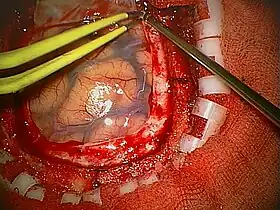

Diagram of the elements of a craniotomy.

Human craniotomy is usually performed under general anesthesia but can be also done with the patient awake using a local anaesthetic; the procedure, typically, does not involve significant discomfort for the patient. In general, a craniotomy will be preceded by an MRI scan which provides an image of the brain that the surgeon uses to plan the precise location for bone removal and the appropriate angle of access to the relevant brain areas. The amount of skull that needs to be removed depends on the type of surgery being performed. The bone flap is mostly removed with the help of a cranial drill and a craniotome, then replaced using titanium plates and screws or another form of fixation (wire, suture, etc.) after completion of the surgical procedure. In the event the host bone does not accept its replacement, an artificial piece of skull, often made of PEEK, is substituted. (The PEEK appliance is routinely modeled by a CNC machine capable of accepting a high resolution MRI computer file in order to provide a very close fit, in an effort to minimize fitment issues, and therefore minimizing the duration of the cranial surgery.)